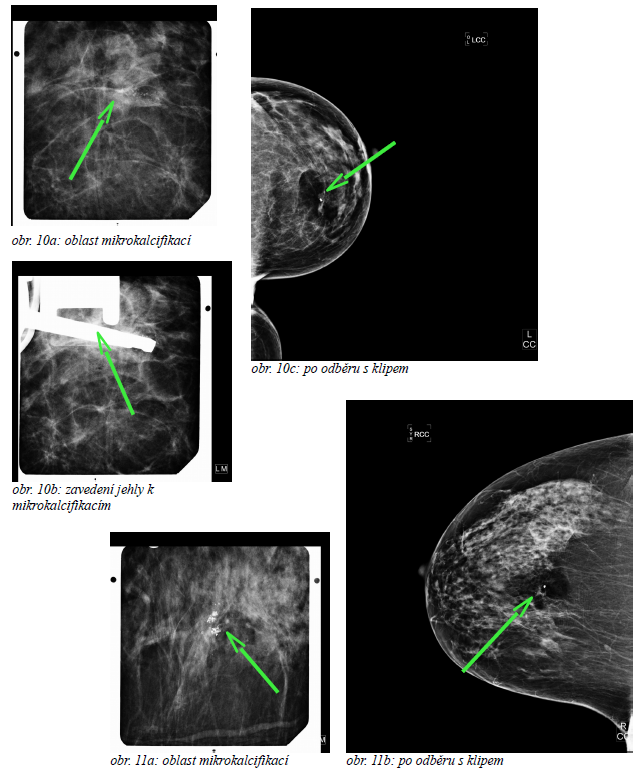

K odběru vakuovou biopsií pod mamografickou kontrolou indikujeme mikrokalcifikace či léze, které pod ultrazvukem nelze zobrazit. (obr. 10a, b, c a obr. 11a, b) Pod ultrazvukovou kontrolou odebíráme přednostně pomocí cut core biopsie, a pouze v omezených, lékařkou indikovaných případech používáme vakuovou biopsii.

V některých případech odebereme i celou lézi či celou oblast mikrokalcifikací. Vzhledem k aplikaci klipu do místa odběru jsme schopni chirurga navést do původního místa odběru.